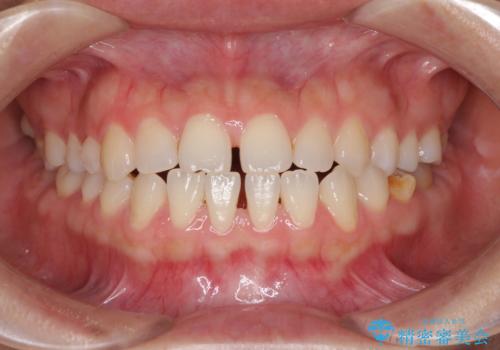

- 上下の前歯の隙間を気にして来院された患者様です。

インビザラインを用い、上下歯列のスペースを閉じていくこととしました。